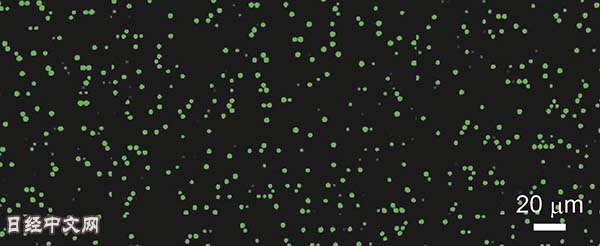

检出病毒后芯片上的微型试管会发出荧光(图片由日本理研提供)

理研等开发的技术是,利用多个微型试管组成的芯片(采用半导体技术制成)来检测病毒。在1平方厘米内排列约100万个试管,在各试管中,试剂与病毒的RNA发生反应时会发出荧光,从而检出病毒。